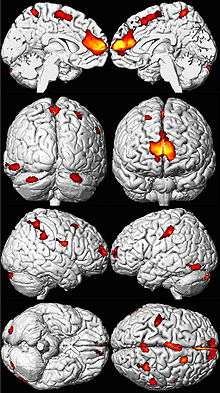

Eight MRI views of a brain in black and white, with yellow, orange, and red areas overlaid in spots mainly toward the front.

The brains of adults who were exposed to lead as children show decreased volume, especially in the prefrontal cortex, on MRI. Areas of volume loss are shown in color over a template of a normal brain.[63]